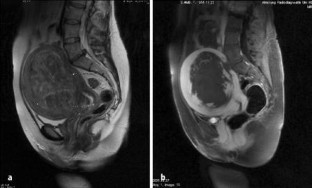

Abb. 1a,b

Abb. 3a–e

Abb. 5a,b